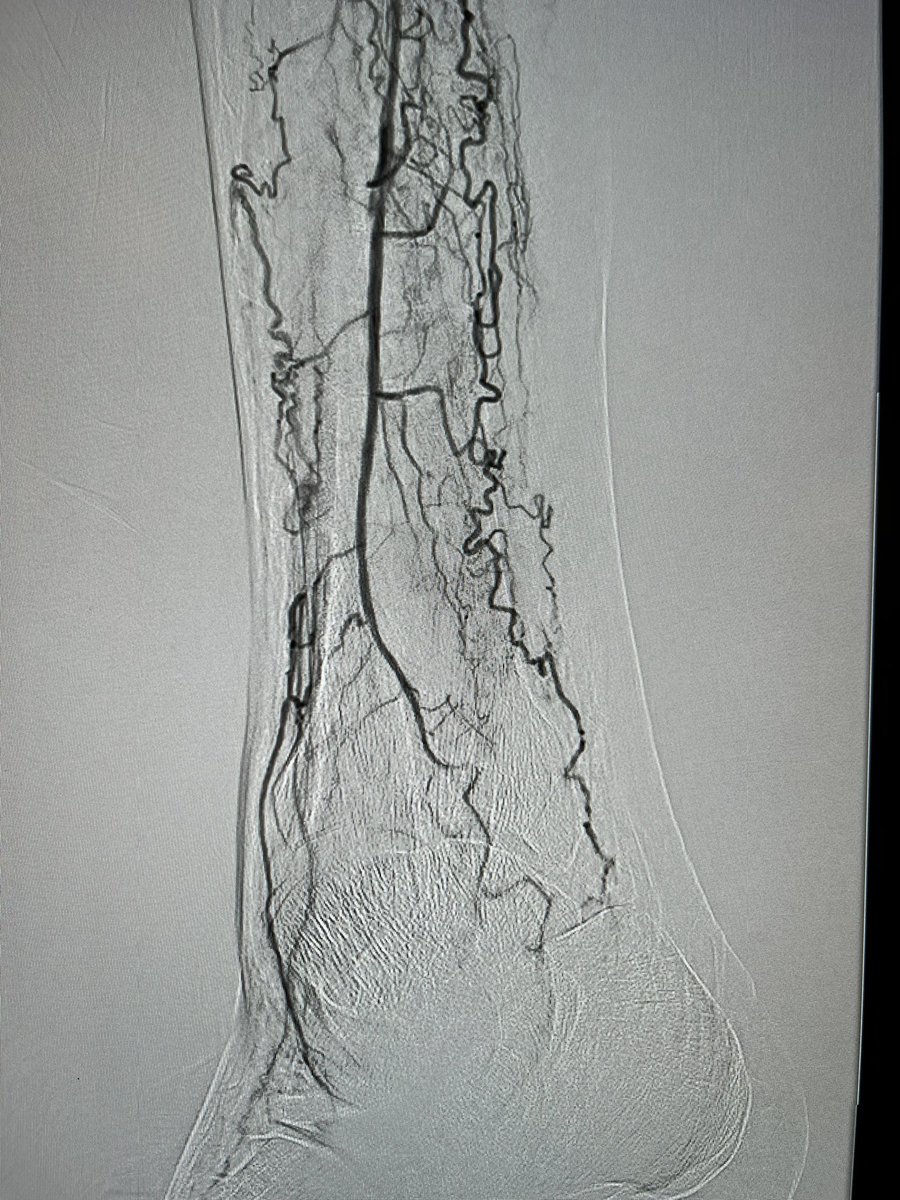

We completed the first 2 perc bypass in Illinois w #Detour @endologix Excited for this groundbreaking technology to be in the hands of #limbsalvage docs around the globe. @ShawnPenn33 @DeanFerreraDO @Abd_Alrifai @MarcoShaker @tlevin @advocatehealth

3

4

13